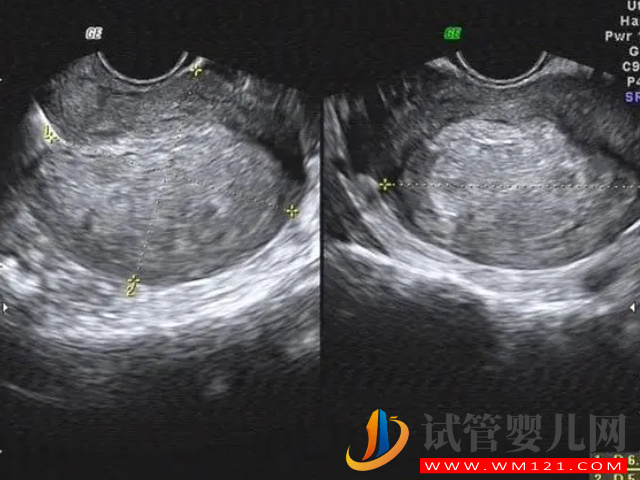

根據(jù)相關(guān)數(shù)據(jù)表明,現(xiàn)目前做試管嬰兒認(rèn)為的最佳子宮內(nèi)膜厚度為8mm-12mm,對于子宮內(nèi)膜厚度的要求是很嚴(yán)格的,因為在移植前都是會檢查的,如果不合格可能就需要先治療,采用凍胚移植,如果不治療就算是移植了,也是會因為子宮內(nèi)膜薄而不著床,或者是正常后出現(xiàn)流產(chǎn)的情況。